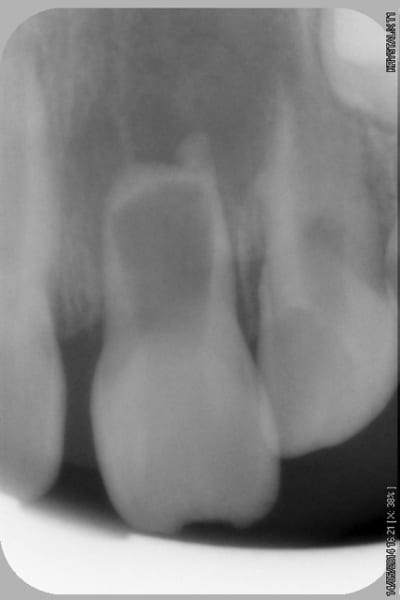

- radios en pièce jointe

- Déterminer par cone beam l'intégrité des parois radiculaires (Y-a-t-il une communication endo paro ou non?)

- Essayer de conserver ce qui reste de la racine par un ttt CaOH ou obturation radiculaire à la biodentine ou au MTA blanc?

- stopper ce qui est vraisemblablement une résorption inflammatoire (faut pas trainer!)

- maintenir l'espace de la 21 (par la 21!)

- maintenir de l'os pour plus tard.